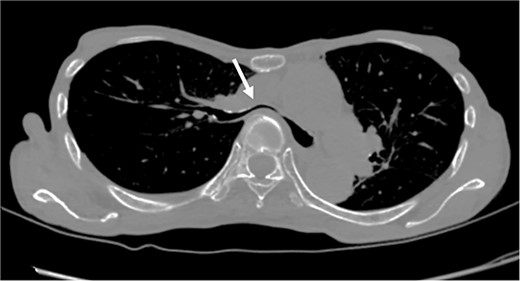

The patient was a 74-year-old woman with a history of childhood PE. Fourteen years ago, a total glossolaryngectomy was performed at another hospital for oropharyngeal cancer, and a permanent tracheal stoma was created. Approximately 2 years later, the patient gradually experienced difficulty in breathing. Chest computed tomography (CT) revealed severe PE and right main bronchial stenosis. Subsequently, the patient was referred to our department. A preoperative spirometry test showed a vital capacity of 1.14 L (45% of the predicted value). As part of the imaging test, a chest CT indicated a leftward deviation of the trachea. Symmetrical depression with a Haller Index (HI) of 8.9 and stenosis of the right main bronchus were observed at the same site (Fig. 1). The chest CT taken over 8 years indicated that the leftward deviation of the trachea had progressed and the thoracic depression had worsened (Fig. 2). Intraluminal observation using a bronchoscopy revealed severe stenosis of the right main bronchus, making peripheral observation challenging (Fig. 4A).

CT scans are used to monitor changes over time. In (A), chest CT findings of severe PE with stenosis of the right main bronchus. The trachea, which was centrally located on CT scan 8 years ago (2B), has shifted to the left now (2A). Additionally, the CT-HI worsened over his 8 years, increasing from 6.8 to 8.9.